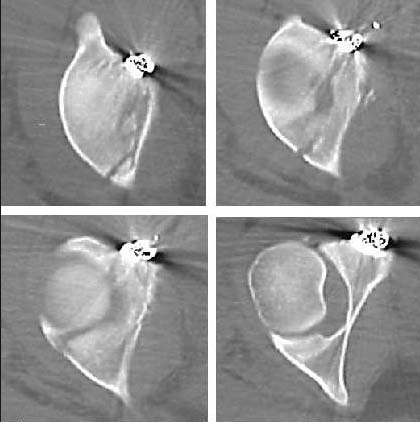

Through this exposure, using a preferential anterior clamp application, the reduction is "eccentric", and this is the result. The transverse fracture's reduction must be "balanced", and then similarly balanced fixation supports such a reduction...the anterior plate as shown does not provide balanced fixation for this particular fracture pattern.